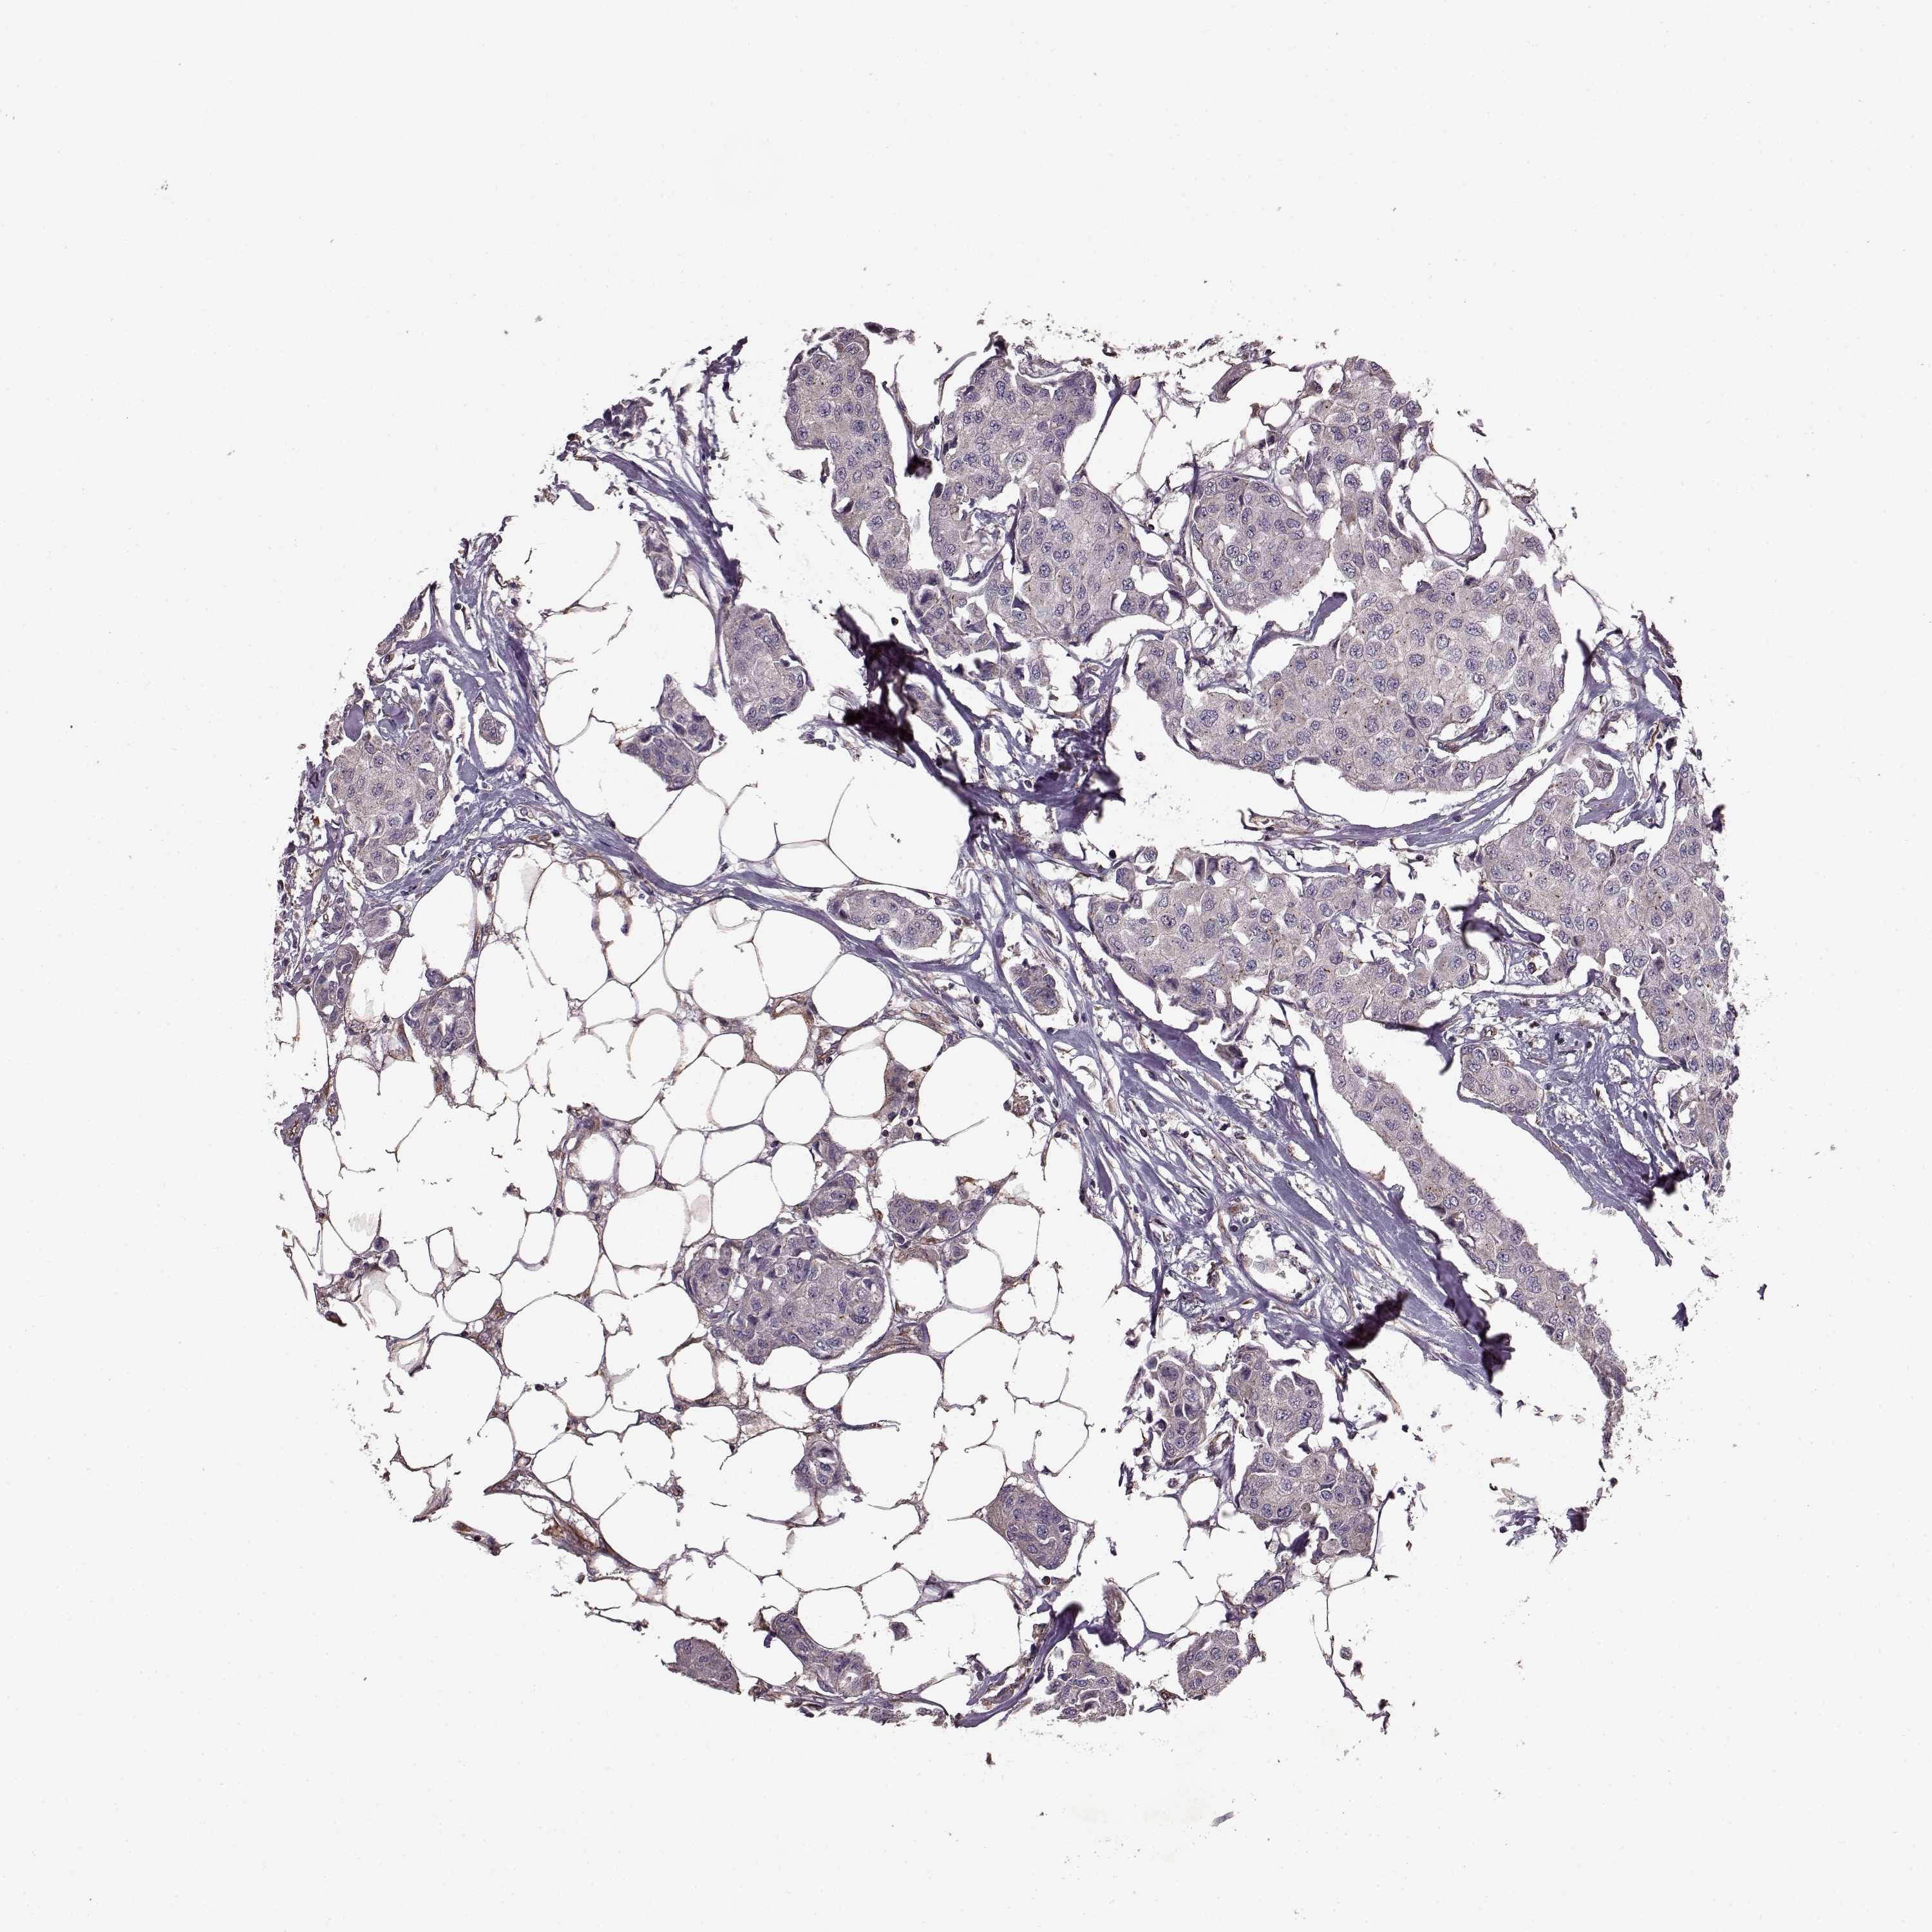

CANCER BREAST CANCER Show tissue menu

BRCA TCGA BRCA VALIDATION PROTEIN EXPRESSION